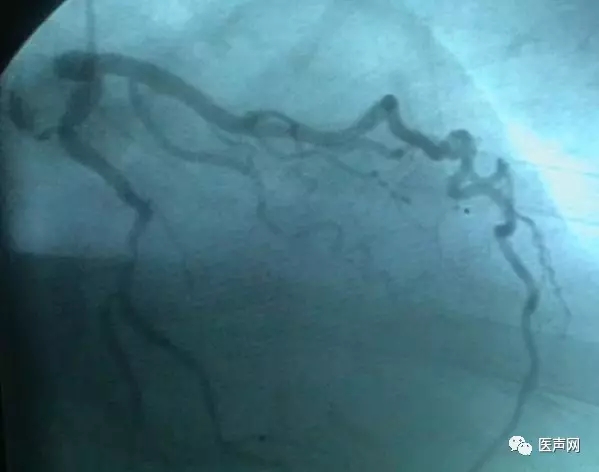

病例3:LAD中段90%狭窄

操作过程:JL4导引导管同轴性不好,支撑力不够,直接支架术(direct stent)有阻力,改用EBU 导引导管---植入TAXCOR 3.0×18mm DES.说明:导引导管的重要性。下图所示: